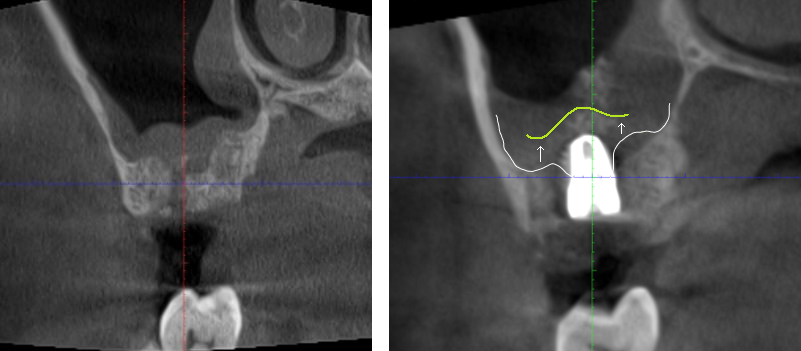

上顎竇增高 前後比較

術後電腦斷層